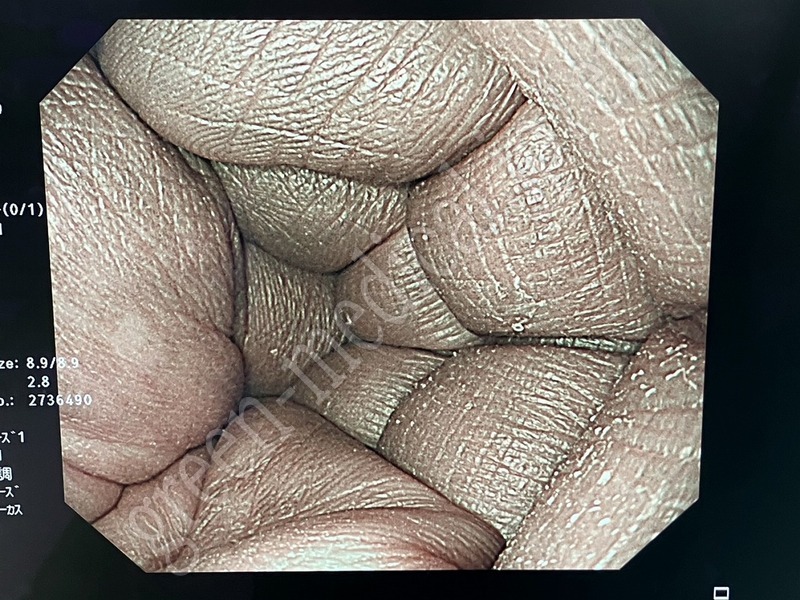

Processor & Xenon Lightsource CV-290・CLV-290

OLYMPUS

CV-290・CLV-290